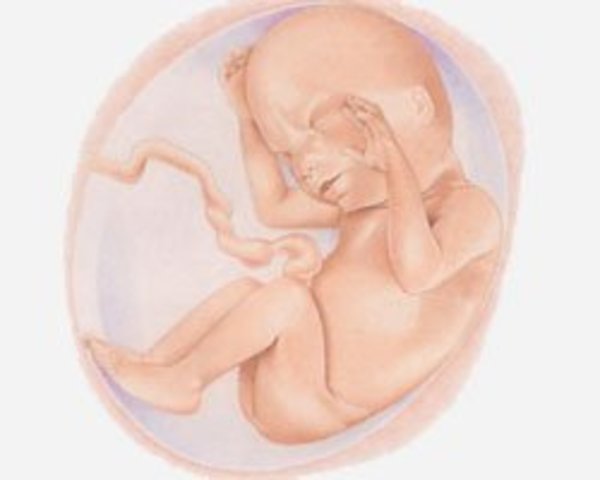

• Semana 27-30

Semana 27-30

En estas semanas el cerebro del bebé está desarrollándose de manera rápida. El sistema nervioso ya puede controlar algunas funciones del cuerpo. El bebé, si así lo quiere, puede volver a abrir sus párpados. El aparato respiratorio, aunque sigue siendo inmaduro, ya produce cierta cantidad de agente vasoactivo que eventualmente ayudará a que los alvéolos se llenen de aire sin impactarse.